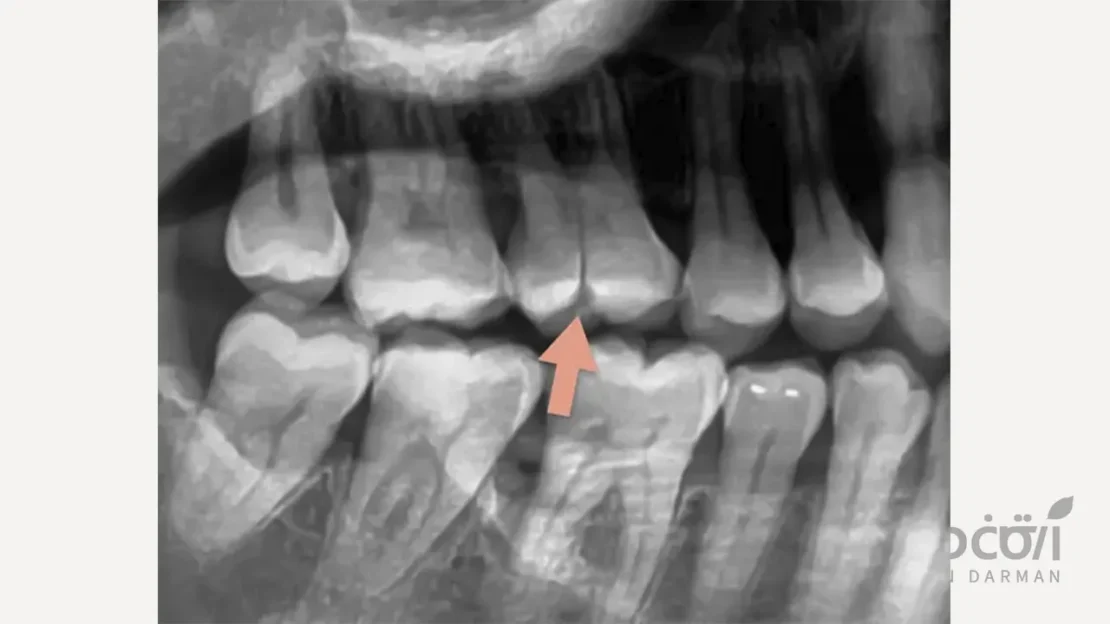

رادیوگرافی و تصویربرداری دقیق

در صورتی که شکستگی در لایههای زیرین یا در ناحیه ریشه باشد، رادیوگرافی با زاویههای مختلف یا سیبیسیتی (CBCT) کمک میکند محل و عمق ترک بهدقت مشخص شود. این تصاویر برای تصمیمگیری درباره نیاز به درمان ریشه یا جراحی حیاتی هستند.